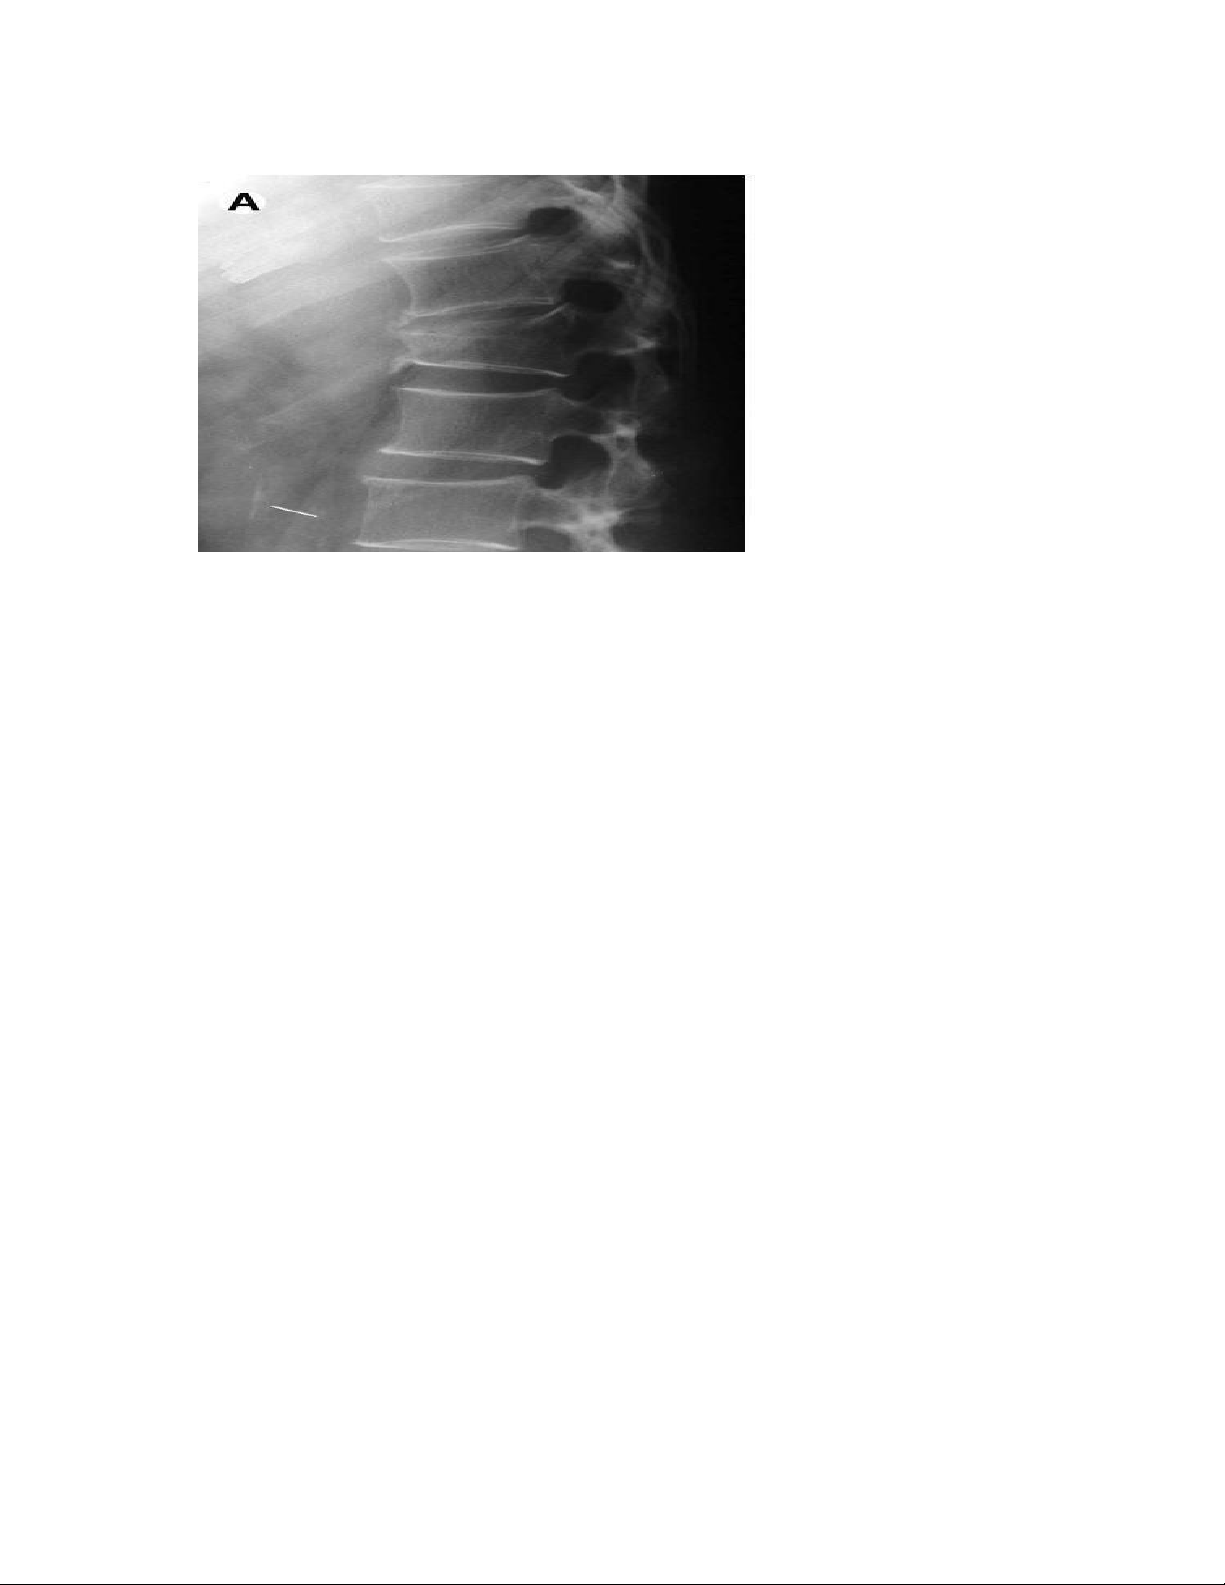

- Xquang quy ước: hình ảnh đốt sống tăng thấu quang, biến dạng thân đốt sống

(gãy làm xẹp và lún các đốt sống), với các xương dài thường giảm độ dày thân

xương (khiến ống tủy rộng ra).

+ Một triệu chứng quan trọng trên XQ là không có tổn thương hủy xương ở đốt

sống(không có hốc, khuyết….) khe liên đốt sống không bị hẹp, các cung sau hầu như bình thường. lOMoAR cPSD| 22014077